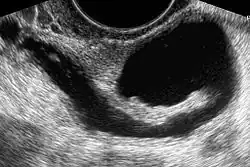

Sonohysterography. The sterile saline instilled into the cavity of the uterus is anechoic (rendered as dark in the middle of the image). It shows a normal endometrium as a hyperechoid (brighter) band around the cavity, in this case without any focal changes.

Sonohysterography is a specialized procedure by which fluid, usually sterile saline (then called saline infusion sonography or SIS), is instilled into the uterine cavity, and gynecologic sonography performed at the same time. A review in 2015 came to the conclusion that SIS is highly sensitive in the detection of intrauterine abnormalities in subfertile women, comparable to hysteroscopy. SIS is highly sensitive and specific test in the diagnosis of uterine polyps, submucous uterine fibroids, uterine anomalies and intrauterine adhesions (as part of Asherman's syndrome), and can be used as a screening tool for subfertile women prior to IVF treatment.[4]